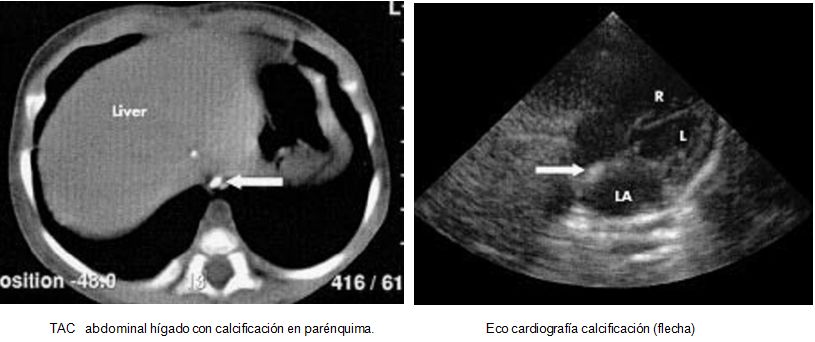

La necrosis grasa subcutánea del recién nacido es un trastorno poco frecuente, que puede ser complicada por hipercalcemia y trombocitopenia. Normalmente es una condición autolimitada, en la que las lesiones cutáneas se resuelven espontáneamente en cuestión de semanas o meses. La hipercalcemia es una complicación de la NGSC, que puede ser potencialmente mortal si no se trata adecuadamente. Se han encontrado en pacientes con NGSC, calcificaciones hepáticas y cardiacas.